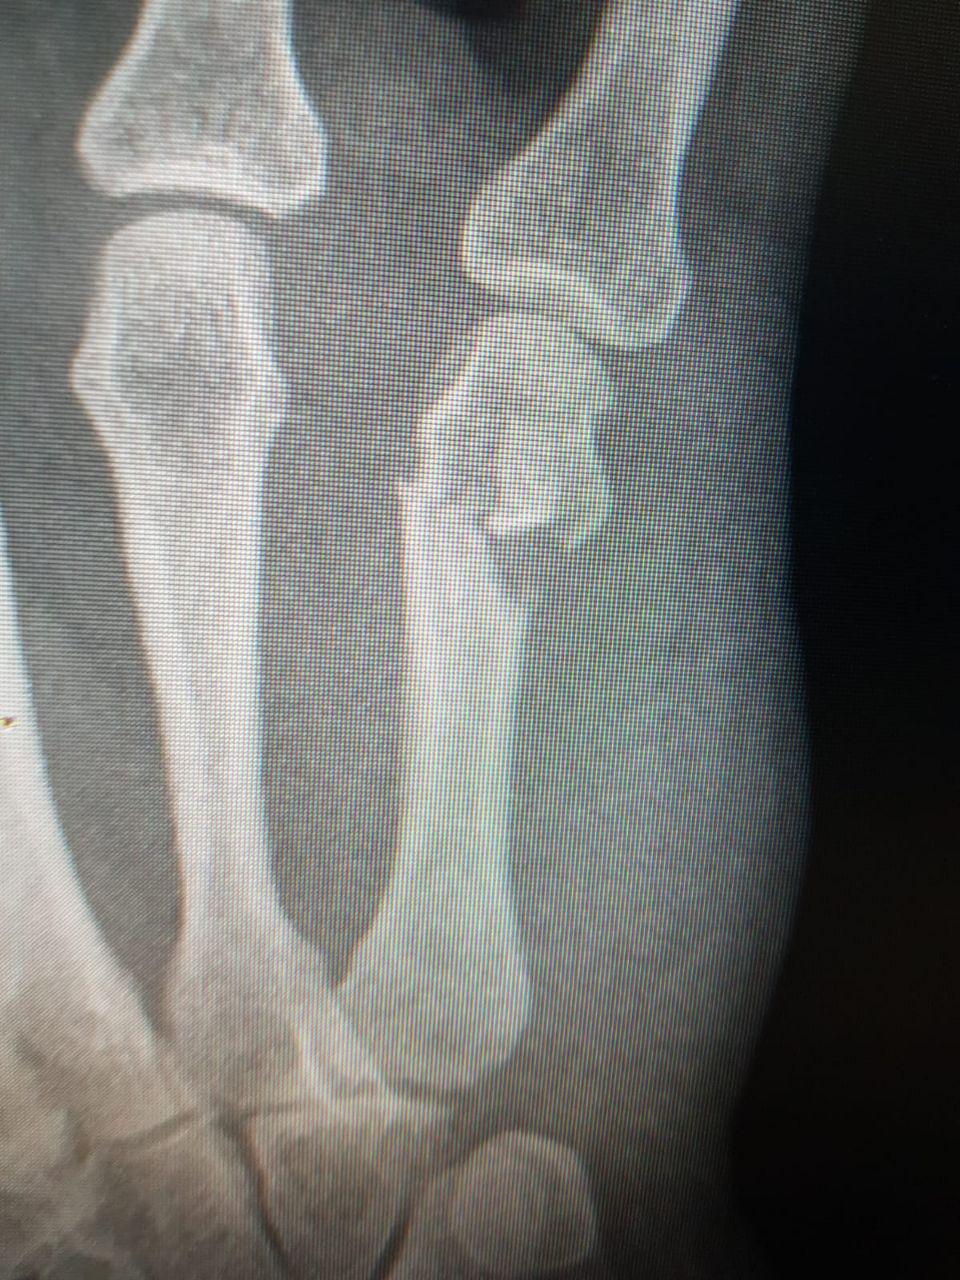

Вскоре домой пришел муж. Он ахнул, увидев Наталью, и повез ее в больницу. Там выяснилось, что кисть сломана в четырех местах.

"На 6 ближайших недель я стала инвалидом, ведь этой рукой я ничего не могу делать. Перелом пальца и множественные переломы ладони – таков диагноз врачей", - заключает Наталья.

Перелом кисти в четырех местах выбил Наталью из колеи надолго. Фото предоставлено пострадавшей